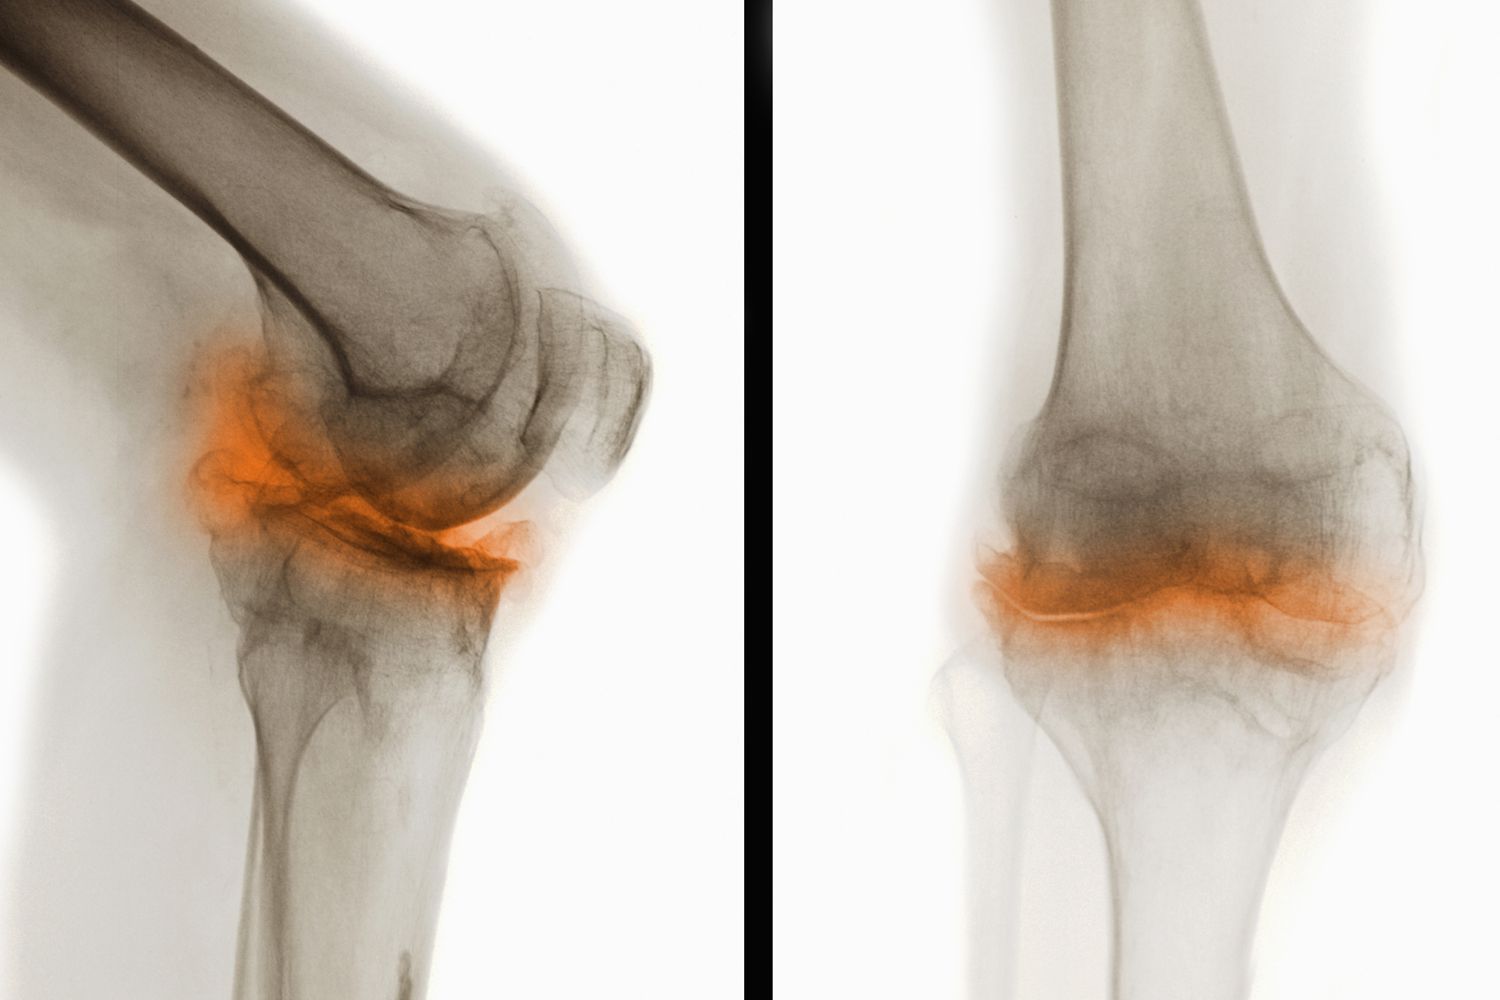

骨關(guān)節(jié)炎(Osteoarthritis,簡(jiǎn)稱OA)是一種常見(jiàn)的慢性退行性關(guān)節(jié)疾病,主要表現(xiàn)為關(guān)節(jié)軟骨的退化和破壞,導(dǎo)致關(guān)節(jié)疼痛、僵硬和功能障礙。這種疾病通常發(fā)生在中老年人群中,尤其是負(fù)重較大的膝關(guān)節(jié)、髖關(guān)節(jié)、脊柱及遠(yuǎn)側(cè)指間關(guān)節(jié)等部位。